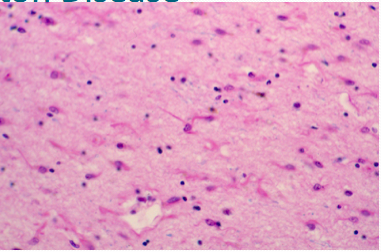

What does the following image show?

Huntington disease:

Hydrocephalus ex vacuo can develop due to loss of tissue in the caudate secondary to the neurodegeneration.